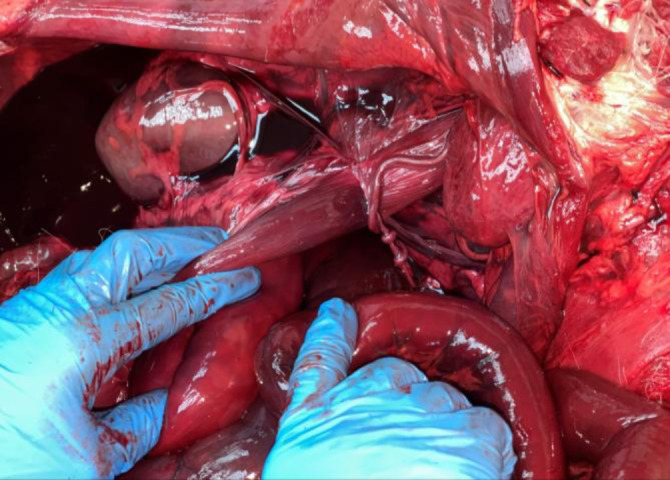

Sudden death has been thoroughly well defined and investigated in human medicine and its definition is not as rigorously established in veterinary medicine. In this case a 7-year-old German Shepherd was brought to the Small Animals Clinic of the Faculty of Veterinary Medicine at the University of Belgrade in very poor state. Despite treatment, the dog died 15 min after being admitted to the clinic. Since poisoning was suspected, the owners requested an autopsy. The dog was taken to the Department of Forensic Veterinary Medicine, Faculty of Veterinary Medicine, University of Belgrade for necropsy. Pathomorphological examinations revealed rupture of the mesentery with mesenteric volvulus. In addition, a large number of adult forms of Dirofilaria immitis were found in the right atrium, ventricle and in truncus pulmonalis. Further examinations of the respiratory system revealed clusters with partially degraded adult parasites in the lobes. The dog died due to mesenteric volvulus which was a rare finding, with an even rarer finding that was lung nodules with adult D. immitis parasites.